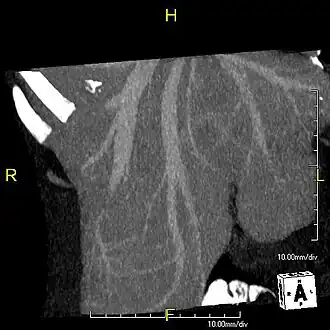

Maximum intensity projection (MIP) CT image as viewed anteriorly showing the anomalous hepatic veins coursing on the anterior surface of the liver -

Lateral MIP view in the same patient as previous image -